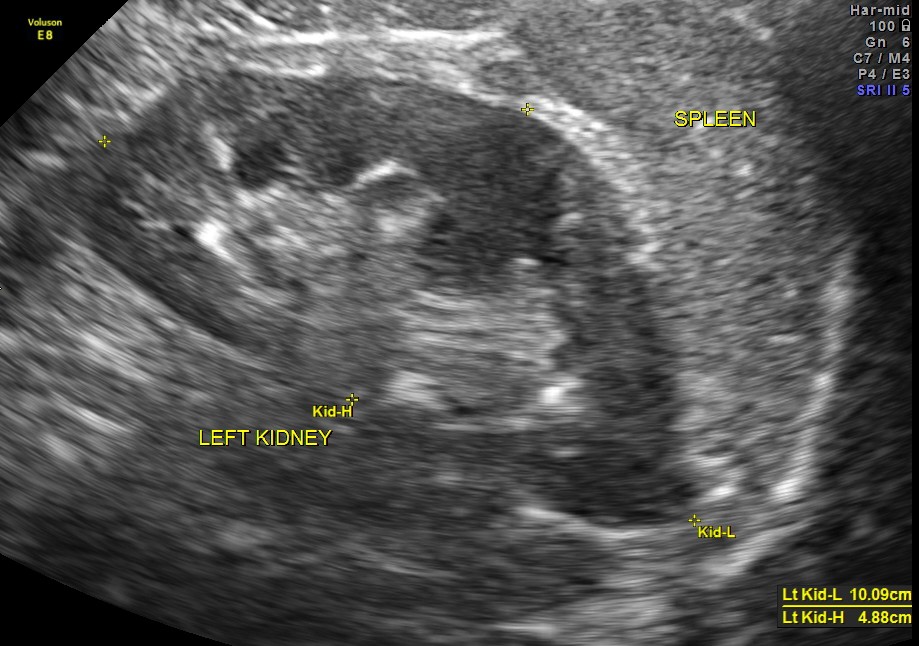

An ultrasound abdomen was done as part of evaluation of anemia.

Now for the unexpected findings . To finish off the scan , I was sweeping the aorta, IVC and the pre and post aortic regions.

This mass visualised there . This was antero-lateral to the aorta and showed mixed echotexture , with some vascularity.

This was not mobile and all i could offer was a description of what was seen with the impression of a mass of unknown origin – ?? enlarged node and advised further work up.